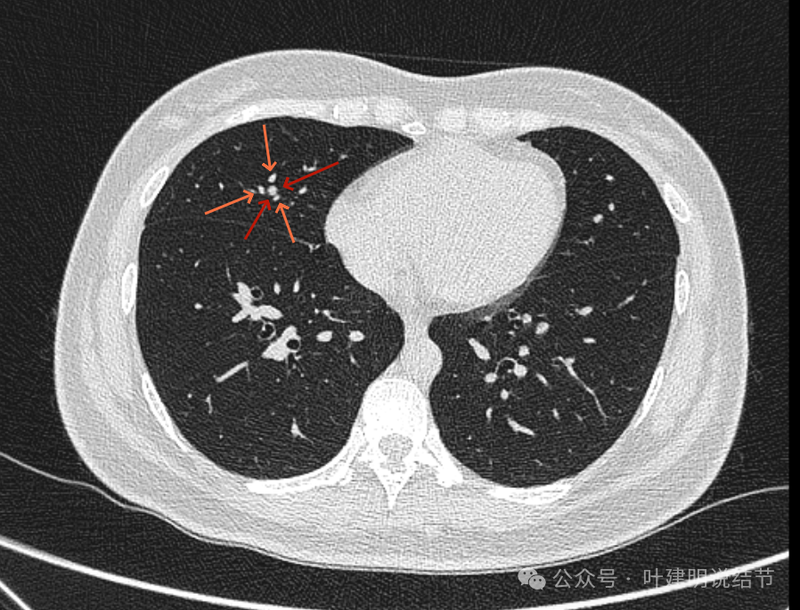

再看冠状位影像:

血管与病灶的关系,两者密度稍不同,天蓝色细箭头所指是分界线。

血管征明显。

血管围着病灶,病灶有膨胀性,表面欠平滑。

不而有膨胀性,血管贴着并被压迫。

边缘欠平滑,邻近血管间隙欠清晰。

血管贴着,结节膨胀。

也示血管与病灶的关系。

结节实性。

纵隔窗这个角度明显见到蓝色箭头所指的血管被病灶侵蚀,而且血管与病灶密度的不同。